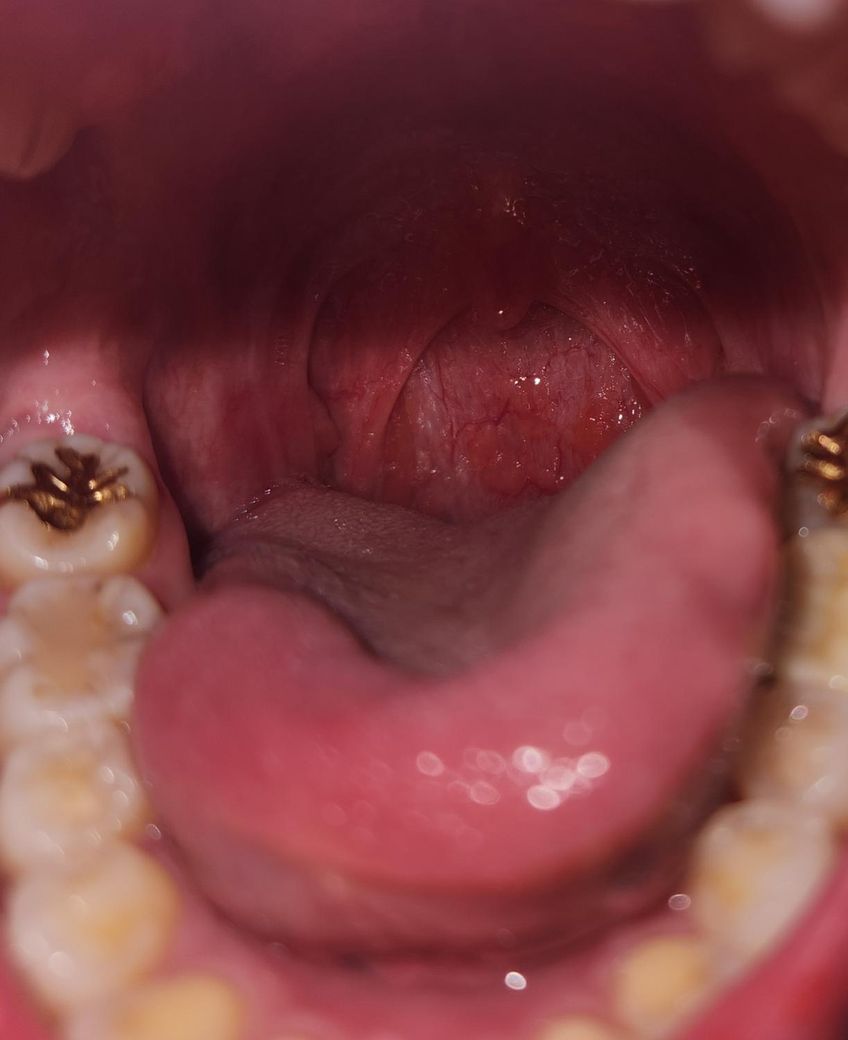

(사진 첨부) 편도암일 수도 있나요..?

몇 달째 목에 간헐적으로 따끔한 통증이 있어요. 오늘은 목에 이물감이 있어 목 안을 봤더니 편도가 사진과 같아요.

튀어나온 부분이 있는데 편도암일 수도 있나요?

올려주신 사진에서 편도는 잘 확인되지 않으나 편도는 큰 문제는 없어 보이며 인두 부위 염증 소견도 뚜렷하지 않습니다.

목의 불편감 때문에 걱정이 되신다면 육안적 진찰을 위해 이비인후과 진료를 받을 것을 권합니다.

인후두부의 질환이 없더라도 역류성 식도염으로 인한 목의 이물감이 생길 수 있으므로 음주, 흡연, 카페인, 탄산음료, 기름진 음식의 섭취, 과식, 식사 후 바로 자리에 눕기 등 악화 요인을 피하고 약물 치료를 받아보시기 바랍니다.

• 안녕하세요. 김지우 의사입니다.편도암이 아니라

편도염이 의심됩니다.

이비인후과 병원에 가서

검사후,

항염증제,항생제 처방 받아서먹으면 호전됩니다.